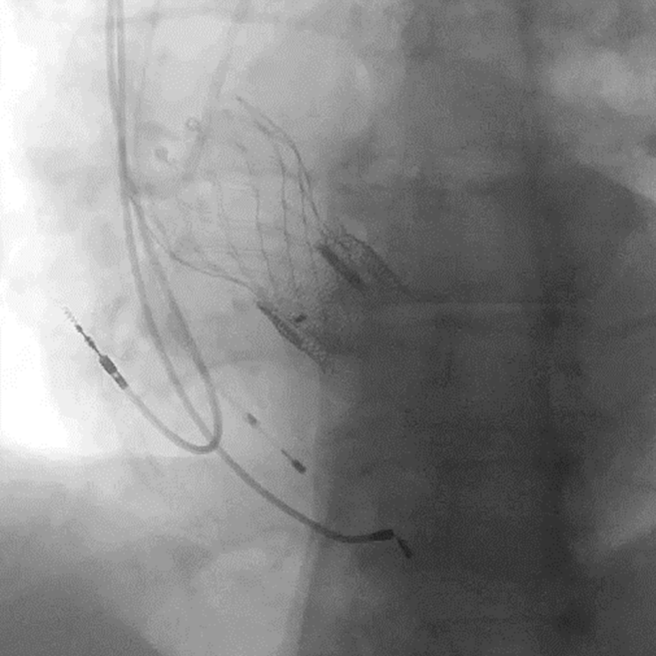

Исходное положение ранее установленных клапанов